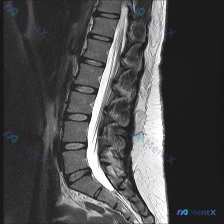

整理了一份网上看到的腰椎MRI病例资料,标注里直接提了“Scoliosis”(脊柱侧弯),但仔细看提供的只有矢状位T2序列。 先把影像核心发现列出来: 1. 椎间盘:各腰椎间盘T2信号普遍减低(黑盘征),提示退变;L4/L5、L5/S1椎间盘后缘明显突出,L5/S1还有向下脱出移位 2. 椎管与神经...

整理到一份影像分析的病例资料,觉得阅片逻辑里有几个坑特别值得拿出来讨论。 资料背景是:患者那边的关注点是「脊柱侧弯」,但目前只拿到了腰椎MRI T2序列矢状位的图像。 先不说侧弯,先放一下这份MRI里明确看到的影像表现: - L1/L2到L3/L4椎间盘信号还行; - L4/L5、L5/S1 是重灾...

整理到一份腰椎MRI T2加权矢状位的读片病例,先抛核心疑问: 有人拿到这份图像首先问「是不是脊柱侧弯」,但实际看下来,图像里的其他征象反而更突出。 先不揭晓后续,只看这份矢状位的描述,大家第一眼会优先关注什么?会不会也先被「侧弯」的主诉带偏?